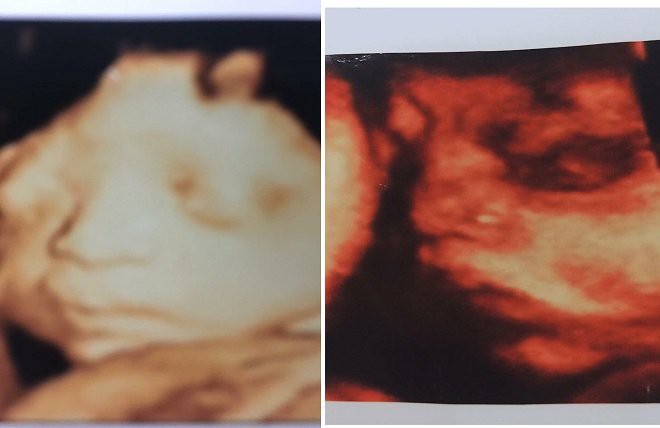

"Đến tháng thứ 3, vợ tôi chụp ảnh gửi phiếu siêu âm về cho tôi xem có tên tuổi của vợ, và hình hài 2 thai nhi. Cũng kể từ đó, vợ tôi đều đi khám 1 mình, rồi lại chụp ảnh con về cho tôi xem", anh L. nói.